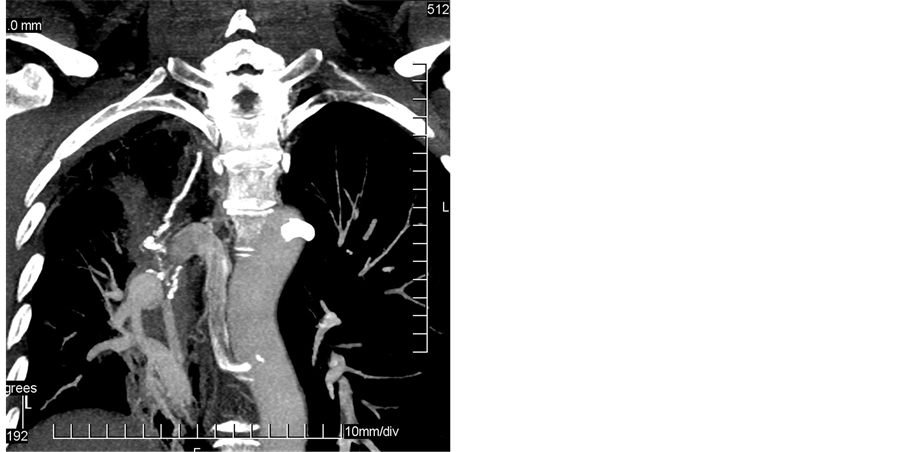

Five bronchial arteries causing hemoptysis had aberrant origin. Two right bronchial arteries arose from the aortic arch. Two left bronchial arteries arose from the descending aorta, outside the T5 - T6 vertebral levels (Figure 3) and one left bronchial artery from the aortic arch.

(a) (b) (c)

Figure 3. (a) Axial 5 mm thick slice CT image in lung window shows cystic bronchiectasis mainly in the left upper lobe. (b) MIP CT image in coronal plane depicts left enlarged ectopic bronchial artery originating from the descending aorta at the level of the T4 vertebral body. This bronchial artery is tortuous and traceable to the hilum. There is also right aortic arch. (c) Selective left bronchial angiogram shows left enlarged bronchial artery with hypervascularity of the left upper lobe.